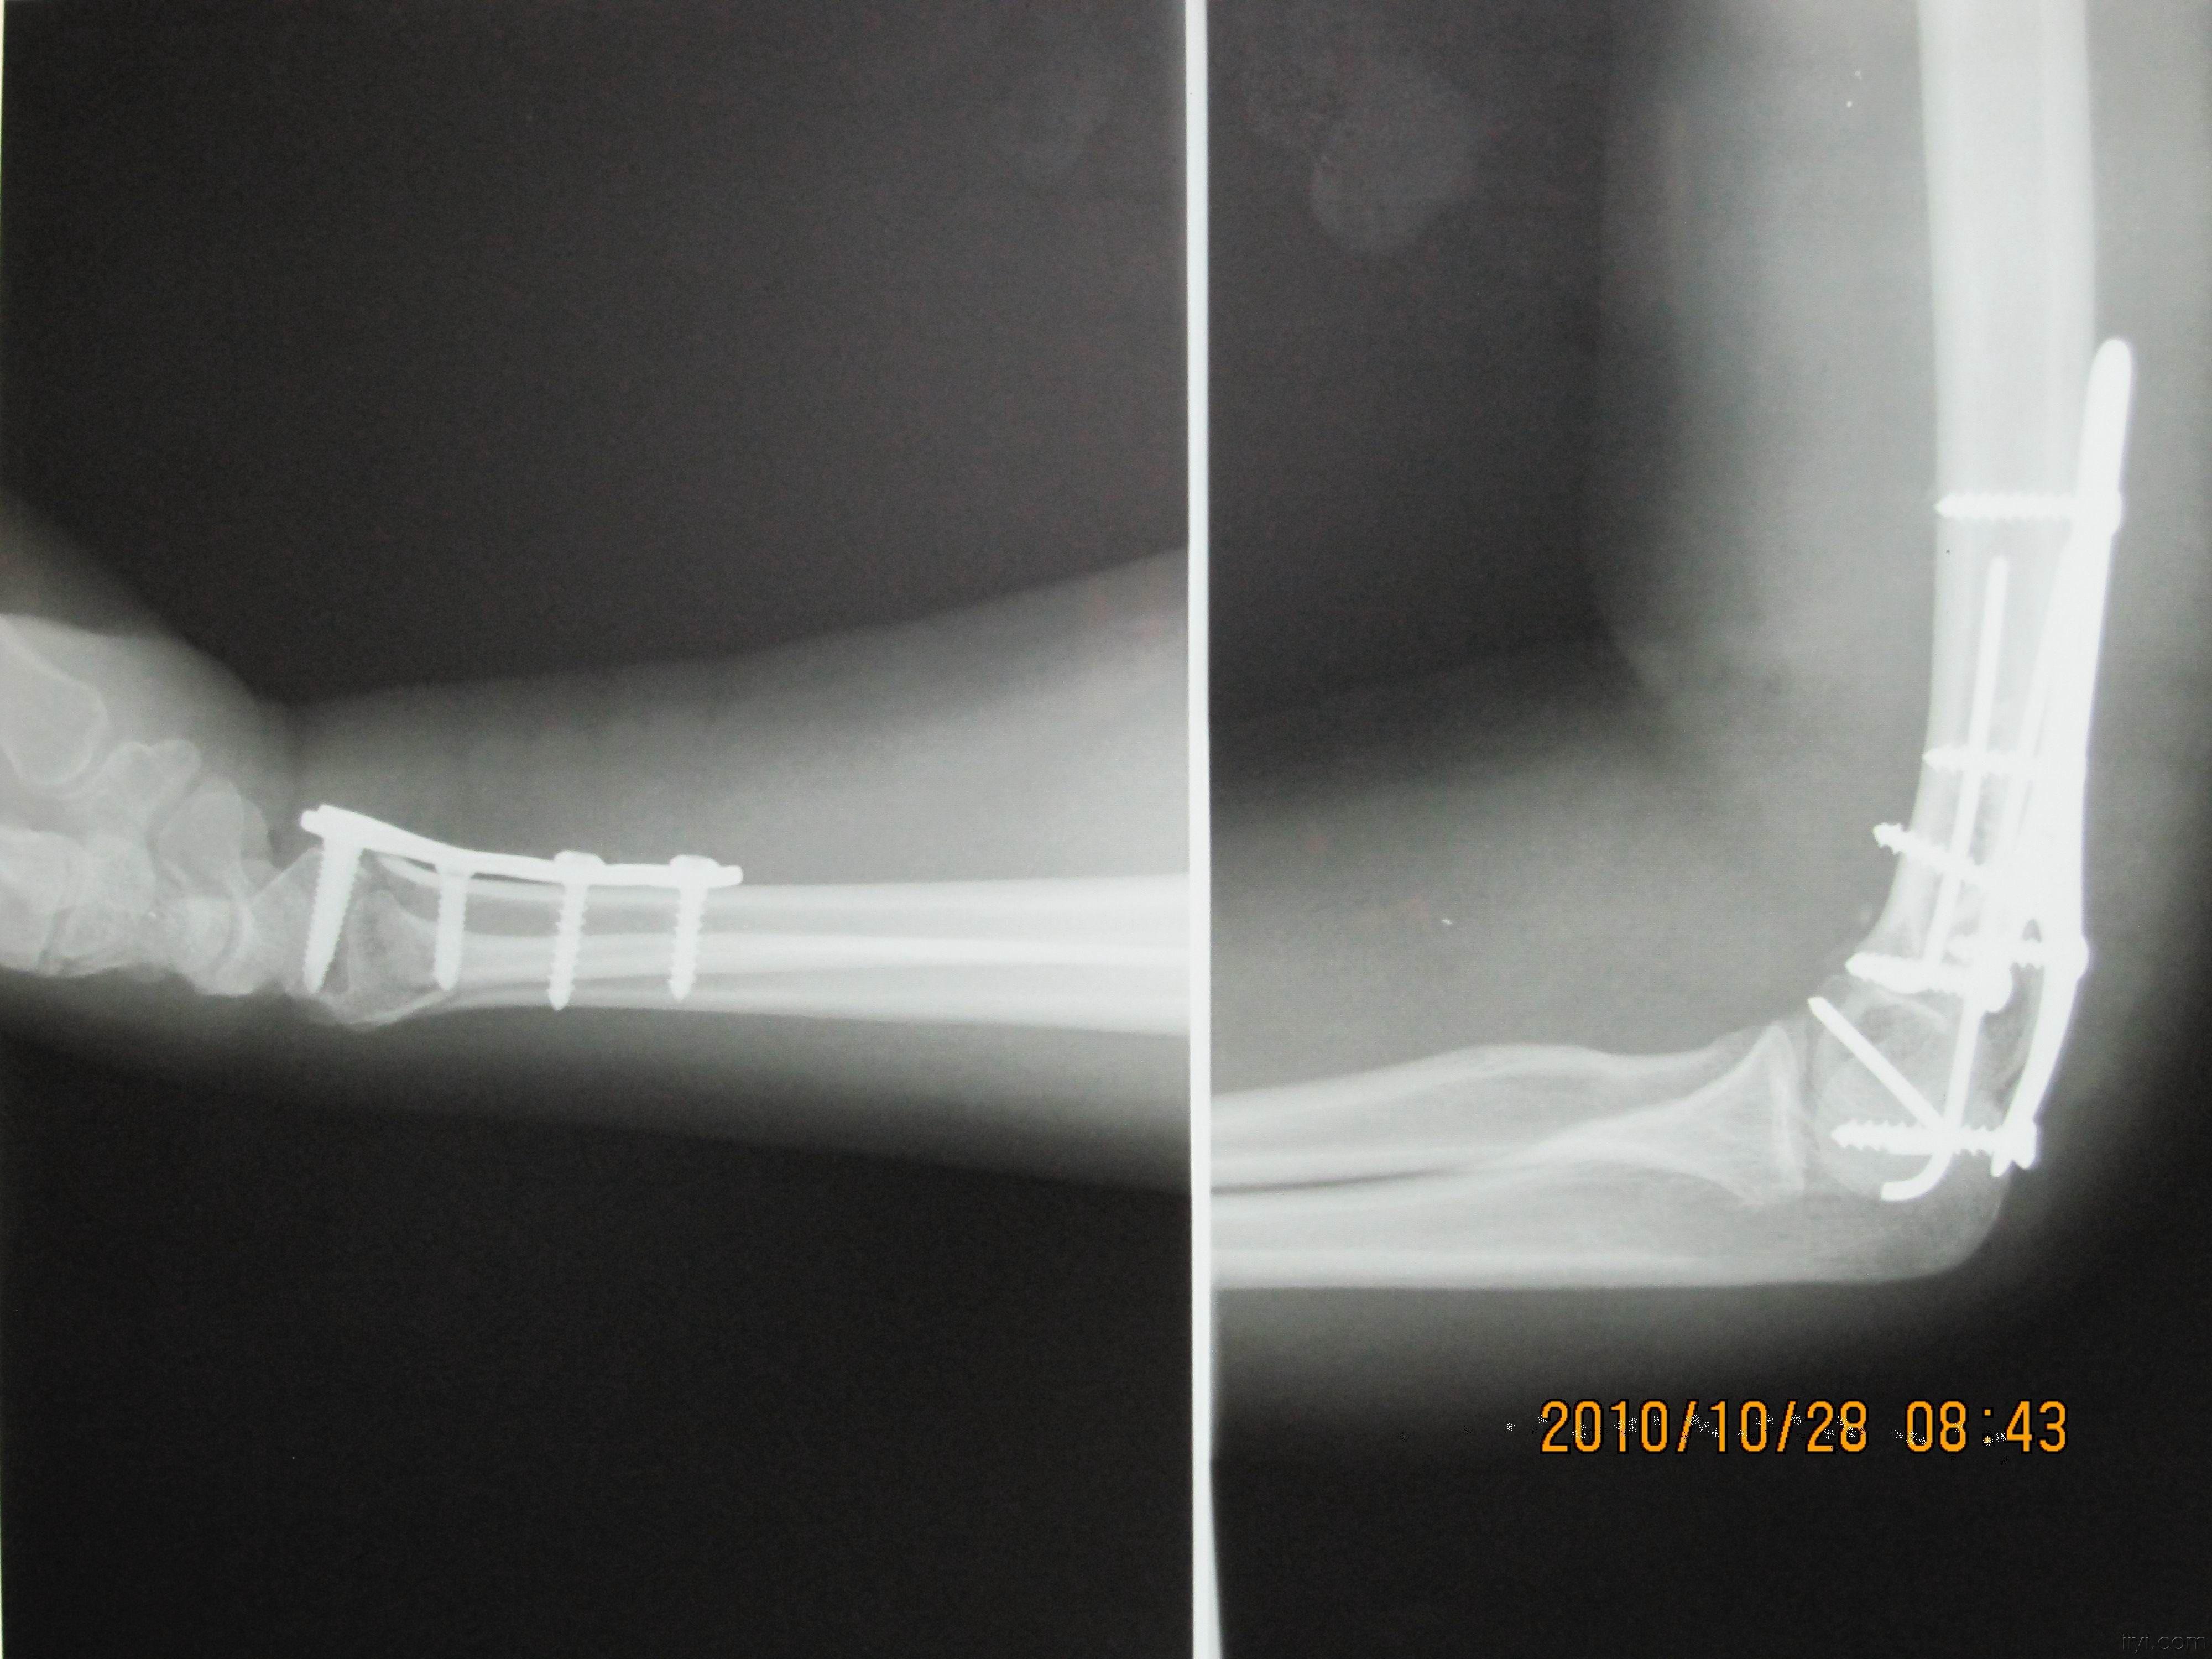

右肱骨干及髁间骨折切复内固定术